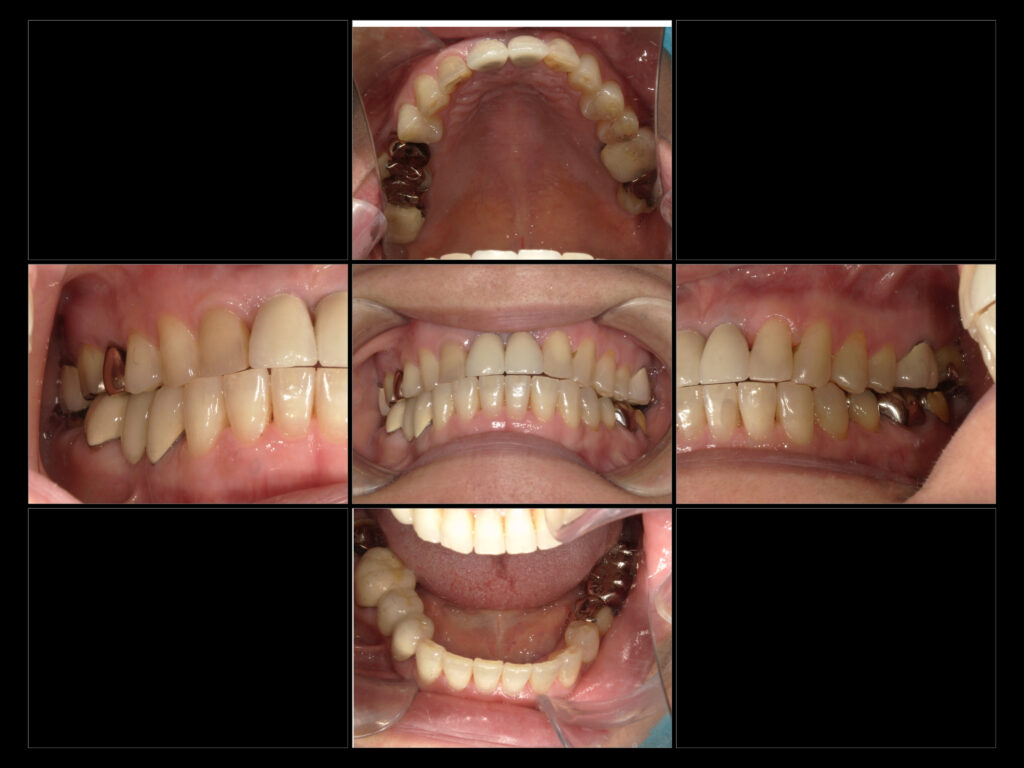

↑初診時口腔内写真

●主訴

右下奥から2番目がかけて物食べると痛む

右下1番奥詰め物取れたところ放置してる